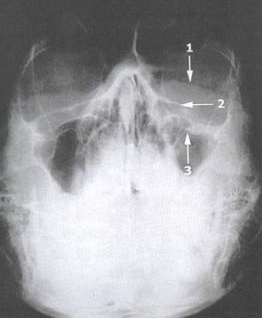

Caldwell View

Evaluation The Upper And Middle Thirds Of The Face